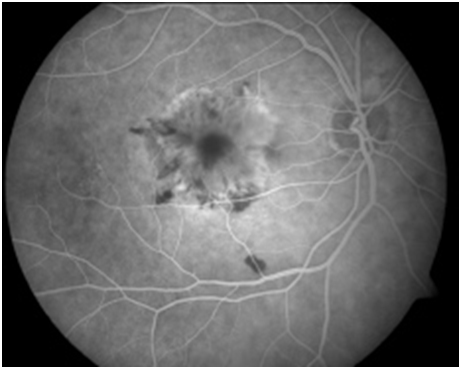

Figure 1A: Late arteriovenous phase angiogram of the right eye demonstrating early hyperfluorescence in the macula. 1B: Late phase angiogram demonstrating leakage from a choroidal neovascular membrane.